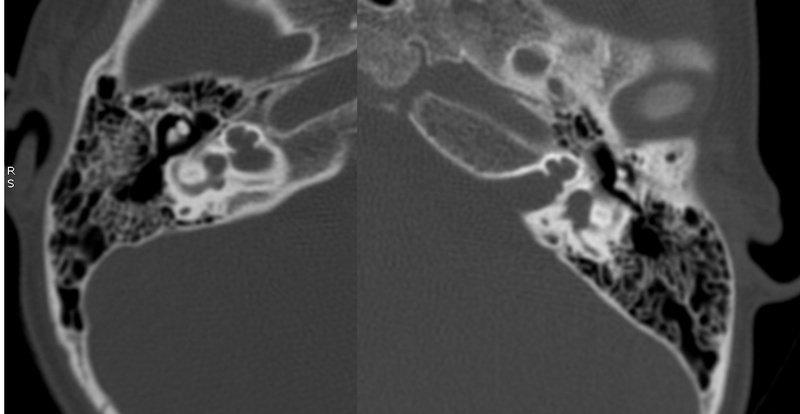

El estudio de imagen se realizó mediante TC de oídos y mastoides. Se aplicaron en cuatro pacientes varones y una madre oyente considerada portadora. Los estudios se clasificaron según Sennanoğlu y cols. [8,9,13].

Evaluación de Imagen (TC)

Los hallazgos radiológicos, mediante TC de oídos a cuatro pacientes varones y una madre oyente, portadora obligada, se analizaron y clasificaron según Sennanoğlu et al. [8,9]. En ese sentido, son consistentes con PI-III en tres de ellos: IV-1, IV -2 y IV- 4. El paciente IV-3 mostró PI-I; la madre portadora obligada no mostró alteración alguna (Ver Tabla 3). En los cuatro pacientes estudiados de esta familia observamos dos tipos de MOI, PI-I y PI-III, incluso entre los hermanos IV-2 y IV-3, que presentaron diferente tipo de PI, lo que evidencia expresividad variable. La malformación PI-III es de las MOI menos frecuente y se encuentra presente en este estudio familiar como predominante.

IV-1. PI-III. HNS severa derecha con curva de perfil irregular, HNS profunda izquierda, con restos auditivos, congénita.

IV-2. PI-III. HNS profunda bilateral con curvas de perfil plano, congénita.

IV-3. PI-I. HNS media bilateral, congénita.

IV-4. PI-III. HNS profunda bilateral, con curva de perfil irregular derecha y plana izquierda, congénita.